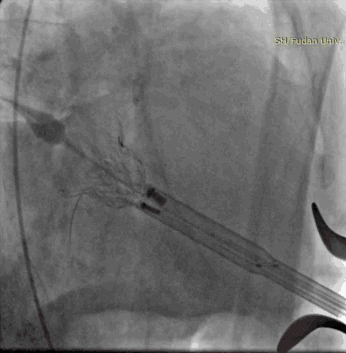

术前左心室造影,二尖瓣重度反流